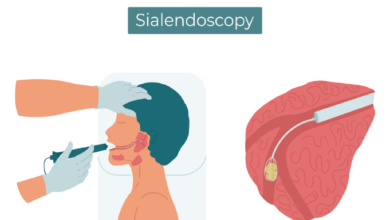

The new DBS system is the smallest ever created. It consists of a tiny battery system for the device, which then delivers electrical impulses directly to targeted areas of the brain, the report said.

To do so, electric probes are put through the skull and deep into the centre of the brain, into the subthalamic nuclei.